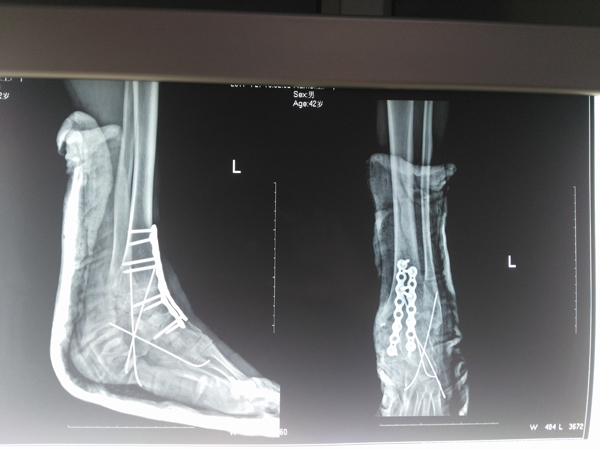

近日,患者到武安市中醫(yī)院進(jìn)行治療。檢驗(yàn)顯示:左踝關(guān)節(jié)形成創(chuàng)傷性關(guān)節(jié)炎,外翻明顯畸形伴有踝關(guān)節(jié)半脫位,距骨脫出,診斷為比較嚴(yán)重的創(chuàng)傷性踝關(guān)節(jié)炎。此種病例的最佳治療方式是進(jìn)行踝關(guān)節(jié)融合術(shù)。于是,骨傷二科醫(yī)生向家屬介紹了病情和手術(shù)的利弊,在征得患者家屬同意后為患者實(shí)施手術(shù)。為了保證質(zhì)量,術(shù)前經(jīng)過(guò)反復(fù)討論,制定了詳細(xì)周密的治療方案,而后,在麻醉科的全力配合下,對(duì)患者如期進(jìn)行了手術(shù)。術(shù)中他們采取前側(cè)口及后縱切口聯(lián)合切口,充分暴露踝關(guān)節(jié)及距骨,將踝穴及距骨做恰當(dāng)?shù)奶幚砗,使距骨充分?fù)位與踝穴對(duì)應(yīng),保持踝關(guān)節(jié)90度位,應(yīng)用鈦扳加以固定,鈦針輔以固定,手術(shù)順利完成。

術(shù)后